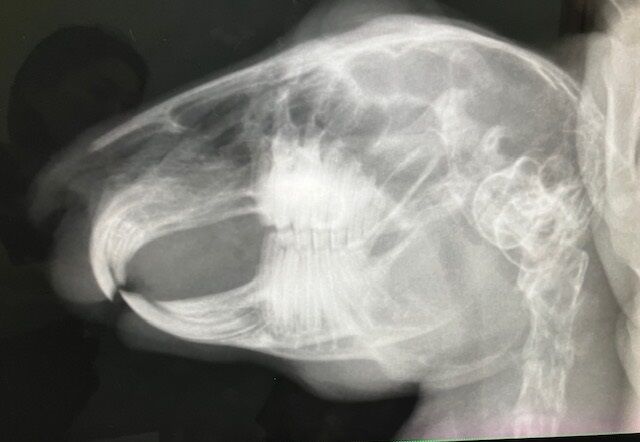

術前検査のレントゲン

特に問題ありません。

※クリックで拡大見れます。

切歯もキレイ